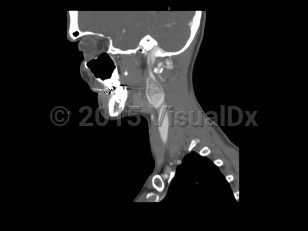

Carotid body tumor

Carotid body tumors / paragangliomas are tumors that arise from cells of the neural crest, particularly in the head and neck, along the carotid body. They can involve other locations. They can present as painless masses but, depending on their location, can cause nerve root compression, pain, and cranial nerve palsies. Treatment involves surgical resection.